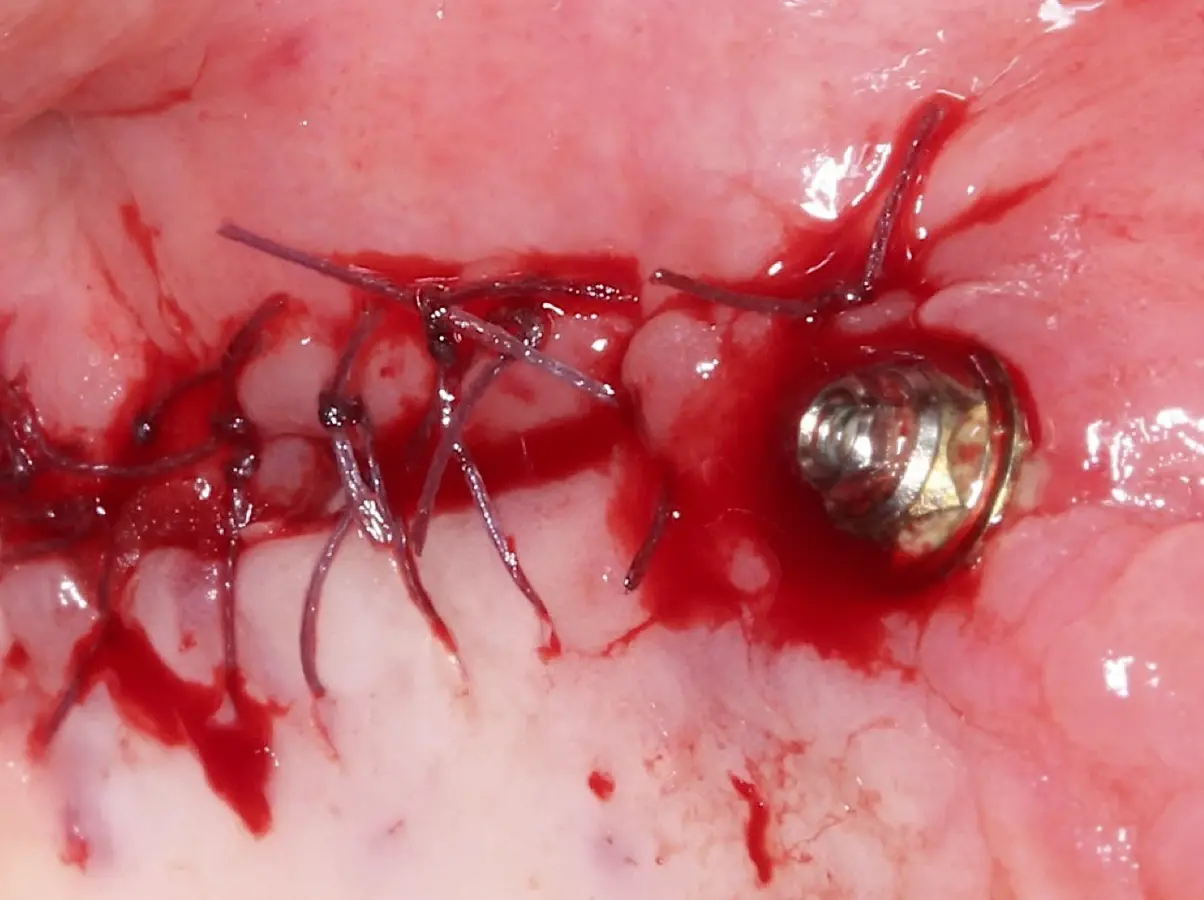

Una vez elevado el piso sinusal según la planificación se realiza la evaluación clínica de la integridad de la membrana y de posibles desgarros a través de la maniobra de Valsalva.24 Consiste en pedir al paciente que respire profundamente y retenga el aire, cerrar la boca, apretar la nariz con los dedos y forzar la salida de aire. Al final de la prueba, es necesario mantener la presión entre 10 a 15 segundos. Se identificará la movilidad de la membrana y la ausencia de burbujas de aire para corroborar que no hay perforaciones. Dependiendo de la decisión clínica se puede optar por adicionar en la superficie de la membrana de Schneider membranas de colágeno o de plasma rico en fibrina (PRF) para dar mayor soporte durante la inserción del biomaterial de relleno óseo (Figura 10).